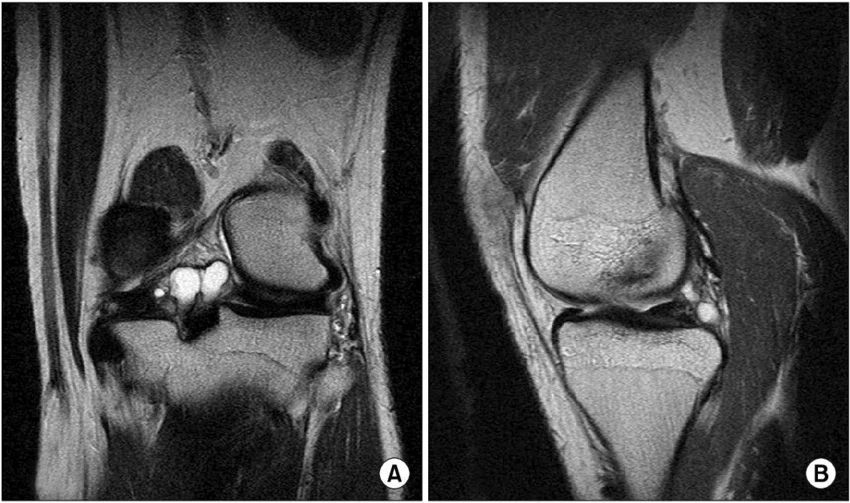

Изображение: researchgate.net/Creative Commons Attribution-NonCommercial 3.0 Unported

- Ядрено-магнитен резонанс (ЯМР): Той е златен стандарт за диагностициране на кисти на мениска. ЯМР показва размера на кистата, наличието на разкъсване на менискуса и други вътреставни патологии.